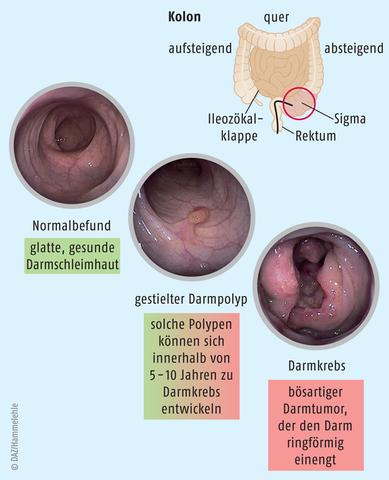

Aus einem Adenom kann sich Krebs entwickeln. Obwohl die meisten Adenome gutartig bleiben und keine weiteren Probleme verursachen, besteht ein gewisses Risiko, dass sie bösartig werden. Es ist wichtig, Adenome frühzeitig zu erkennen und zu behandeln, um das Risiko einer malignen Transformation zu minimieren. Daher werden regelmäßige Untersuchungen und Screenings empfohlen, insbesondere bei Personen mit einem erhöhten Risiko für Adenome oder Darmkrebs.

Ja, aus einem Adenom kann sich Krebs entwickeln. Obwohl ein Adenom anfangs gutartig ist, besteht das Risiko, dass sich einige dieser Wucherungen zu bösartigen Tumoren weiterentwickeln. Dies geschieht jedoch nicht in allen Fällen. Es ist wichtig, regelmäßige Untersuchungen durchzuführen und verdächtige Adenome frühzeitig zu erkennen und behandeln zu lassen.

Obwohl Adenome grundsätzlich als gutartig eingestuft werden, besteht bei ihnen das Risiko, dass sie sich zu bösartigen Tumoren entwickeln können. Es ist wichtig, Adenome regelmäßig ärztlich überwachen zu lassen und gegebenenfalls entsprechende Behandlungsmaßnahmen zu ergreifen, um das Risiko einer Krebsentwicklung zu minimieren.

Obwohl Adenome grundsätzlich gutartig sind, besteht das Risiko, dass sie sich zu bösartigen Tumoren entwickeln können. Einige Adenome haben ein höheres Krebsrisiko als andere, abhängig von ihrer Lage und anderen Faktoren. Daher ist es wichtig, Adenome regelmäßig ärztlich kontrollieren zu lassen und gegebenenfalls zu behandeln, um das Risiko einer malignen Entartung zu minimieren.

Obwohl Adenome grundsätzlich als gutartig gelten, besteht dennoch das Risiko, dass sich aus einem Adenom Krebs entwickeln kann. Dieses Risiko variiert je nach Art des Adenoms und seinem Standort im Körper. Einige Arten von Adenomen haben ein höheres Potenzial zur Entartung als andere.